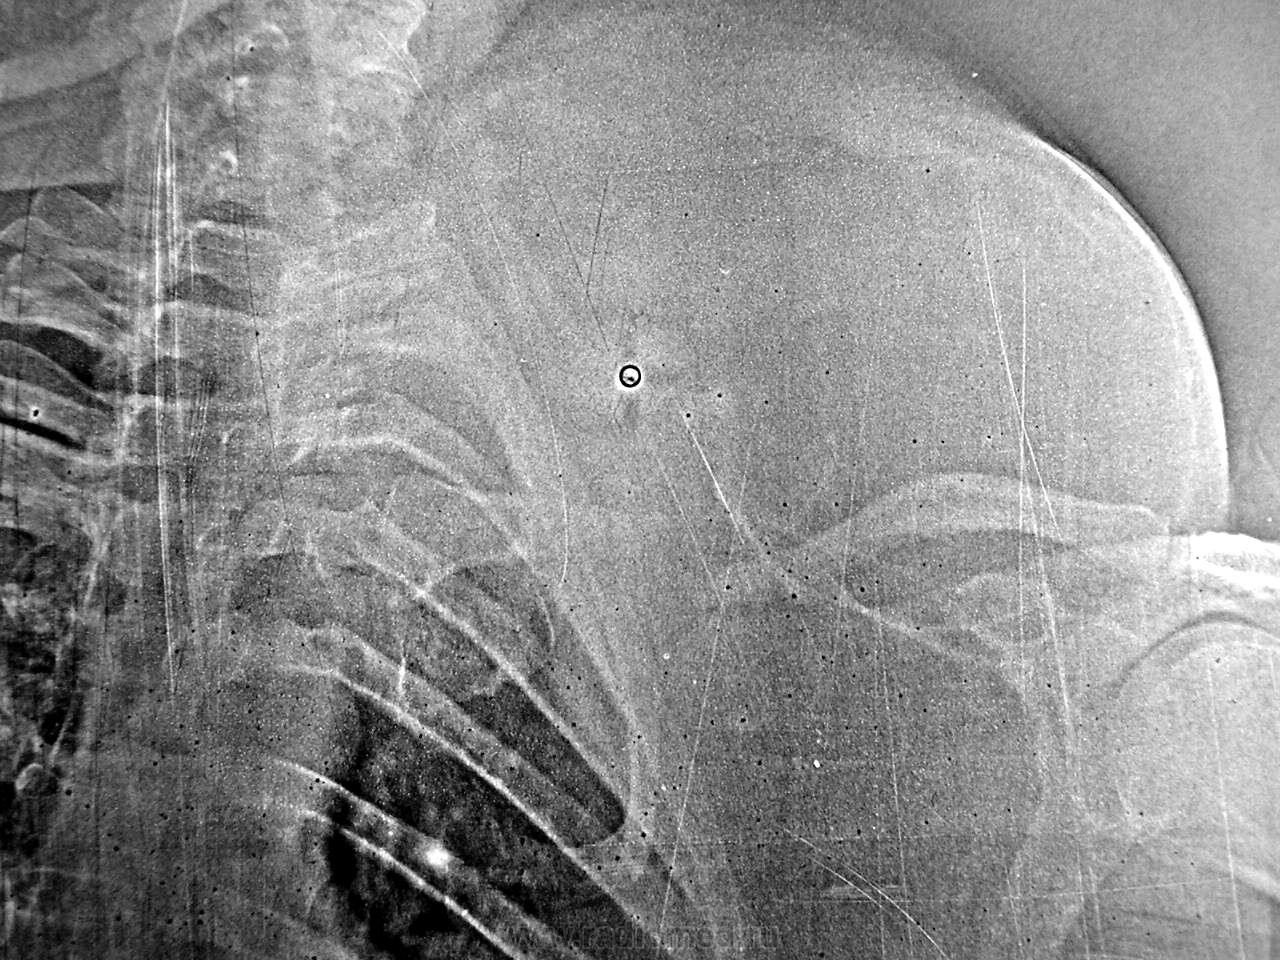

Опухоль над ключицей около 1,5 лет, боли до травмы не было, травма несколько дней назад. Снимок единственный.

Отмеченное не патологическое костеобразование?

К сожалению электрорентгенограммам была свойственна избыточная готовность к артефактам...

Смею предположить больших размеров липому, длительное сдавление ключицы....травма усугубила состояние...перелом как перелом...

А нет ли ещё скорлупообразного обызвествления вдоль наружного контура?

Я это наблюдение представил как редкое по гиганским размерам и вызвавшее атрофию ключицы от давления, с последующим ее патологическим переломом. Это был первый год моей работы (1976), мы осваивали ЭРГ и делали подряд снимки на бумаге и пленке. Включений и обызвествлений на пленочном снимке не было. Образование наощупь - горячее, деревянистой плотности, я для себя решил, что это что-то типа фибросаркомы, но диагноз остался неясен. Дело было в областной больнице, после оказания помощи при травме пациентку перевели в онкологический диспансер. Судьба и гистология неизвестны.